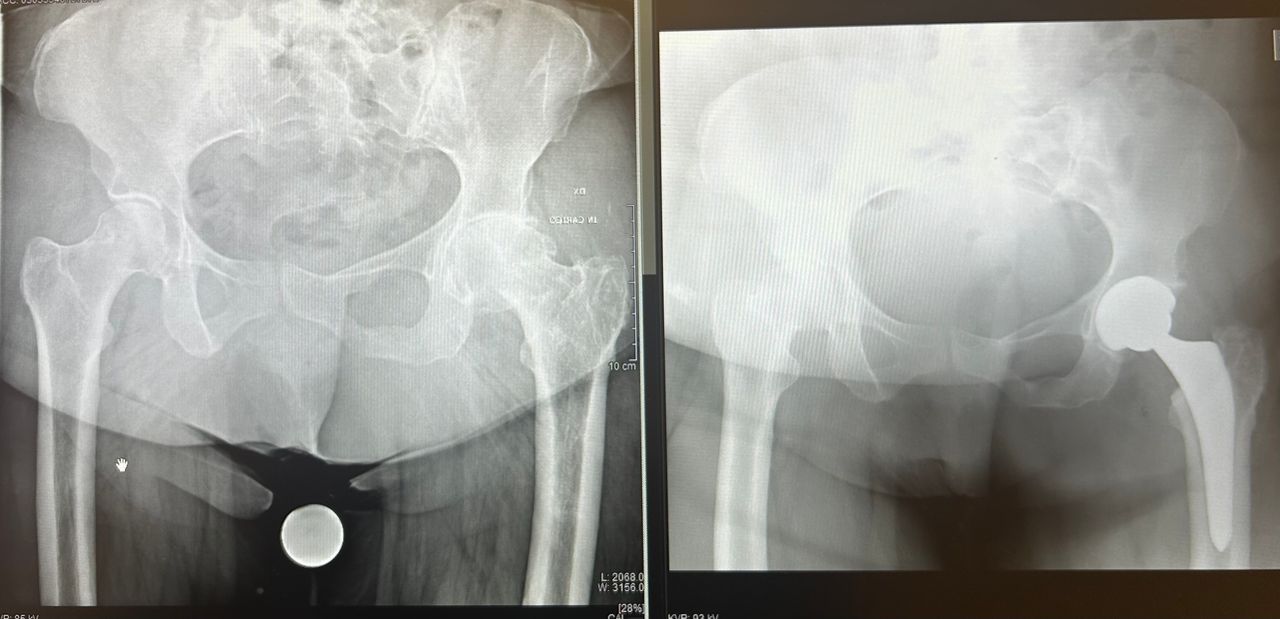

• Chirurgia dell'anca

Per una maggiore completezza della visita è utile avere a dispozione almeno una Radiografia standard o Risonanza Magnetica recenti.

Il dottore Luciano è un ortopedico in cui si coniugano perfettamente professionalità, umanità e grande attenzione, merce rara! Ho effettuato protesi completa di anca e femore in chirurgia miniinvasiva.

Intervento riuscitissimo(e il mio era un caso piuttosto complesso!), ho camminato bene dai primi giorni, il dottore, con eccesso di scrupolo, ha seguito il decorso e le medicazione fino alla completa guarigione, sempre reperibile per qualsiasi imprevisto. Immensamente grata.

Il Dottor Luca Luciano si è dimostrato un professionista di grande competenza e umanità. Fin dal primo incontro ha saputo spiegare con chiarezza ogni dettaglio dell’intervento all’anca, rassicurandomi e facendomi sentire sempre seguito.

Nonostante il mio fosse un caso complesso, ha affrontato la situazione con sicurezza e determinazione, proponendo un intervento di protesi d’anca con tecnica mini-invasiva. Il decorso è stato sorprendentemente rapido e il risultato finale eccellente.